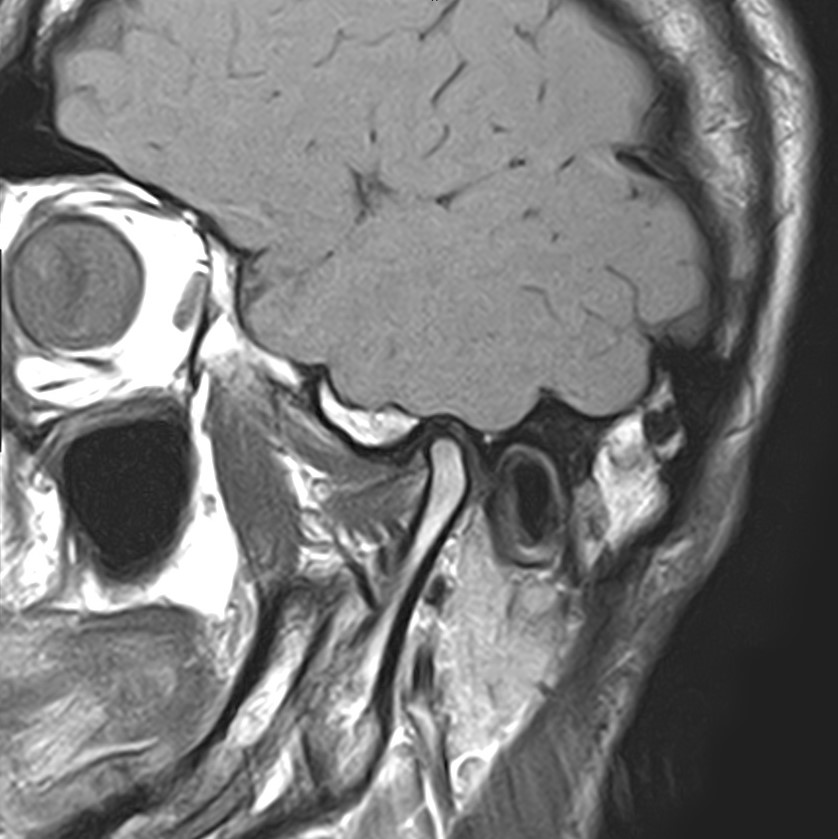

Височно-нижнечелюстной сустав является парным комбинированным суставом и имеет сложное строение. В него входят суставные ямки височной кости, суставные головки нижней челюсти и расположенные между ними хрящевые пластинки – мениски, выполняющие роль амортизаторов.

Чаще всего дисфункция височно-нижнечелюстного сустава обусловлена внутренним повреждением, смещением мениска и суставной головки нижней челюсти. Для определения степени смещения внутрисуставных структур выполняется функциональная проба с проведением МРТ в двух положениях:

• с закрытым ртом;

• с открытым ртом.

Магнитно-резонансная томография является наиболее точным и эффективным методом диагностики поражения височно-нижнечелюстных суставов, так как позволяет получить детальную информацию о состоянии не только костей, но и связочного аппарата, хрящей, менисков, жевательных мышц, окружающих мягких тканей.

При проведении магнитно-резонансной томографии на изображениях визуализируются: височная кость, головка мыщелкового отростка нижней челюсти, суставная щель. Помимо костных структур МРТ позволяет оценить состояние мягких тканей – внутрисуставного диска и связочного аппарата височно-нижнечелюстного сустава, жевательных мышц.